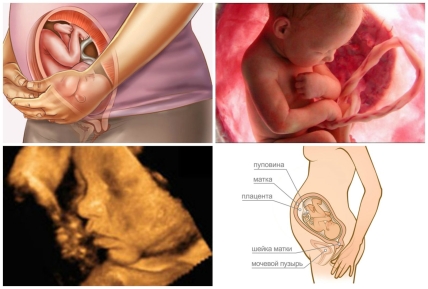

На 36 неделе беременности длина плода составляет 47 см., а вес около 2800 г. К этому периоду малыш уже накопил достаточное количество подкожного жира и выглядит довольно упитанным. Его кожа стала розовой и бархатистой, практически лишена пушка лануго и лишь местами покрыта первородной смазкой. Волосики на голове стали немного длиннее, хорошо заметны брови и ресницы. Ногти на руках и на ногах уже покрывают ногтевые ложа. Хрящи, формирующие ушные раковины, стали заметно плотнее, образованы все завитки и углубления наружного уха.

На таком сроке малышу уже достаточно тесно в полости матки, его движения ограничены, а толчки и удары ощутимы для мамы. Плод занял свое «законное» положение, и оно сохранится до конца беременности. Головка или таз малыша постепенно начинает опускаться в полость таза женщины.

Сердце ребенка бьется с частотой 140 ударов в минуту, его тоны стали четкими и хорошо различимыми в акушерский стетоскоп. В легких содержится достаточное количество сурфактанта. В случае рождения на 36 неделе ребенок будет способен выжить самостоятельно, без поддержки материнского организма и специальной медицинской помощи.